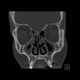

Paranasal sinusitis

Sinusitis, also known as rhinosinusitis, is inflammation of the mucous membranes that line the sinuses resulting in symptoms that may include thick nasal mucus, a plugged nose, and facial pain. Other signs and symptoms may include fever, headaches, a poor sense of smell, sore throat, and a cough. [Source: Wikipedia ]